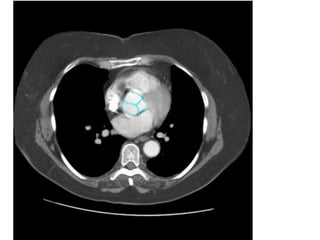

Figure 9. PE ở bn nữ 42 tuổi, đau ngực và khó thở nhiều.

- Hình ảnh thất phải dãn lớn hơn thất trái.

12